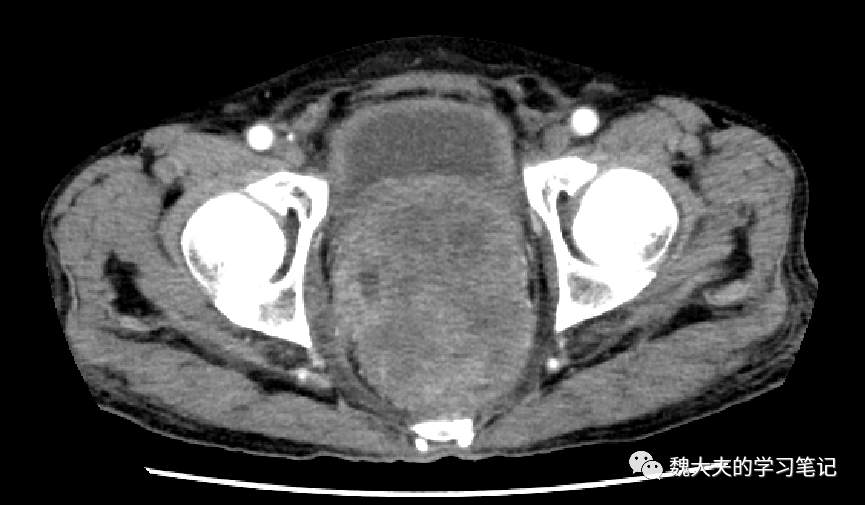

影像学资料:

图片

术前CT增强提示直肠乙状结肠占位,侵犯前列腺及膀胱底部,双肾盂扩张,输尿管积水